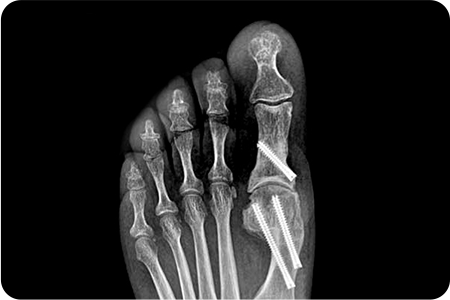

과거에는 튀어나온 뼈만 깎는 수술을 해서 통증도 심하고 재발하는 경우도 많았지만

최근에는 엄지발가락과 인대를 일자로 잡아 주는 절골술을 시행하여 재발률을 크게 낮췄습니다.

엄지발가락 부위에 약 2~3mm 크기의 작은

구멍을 만들고 특수한 미세 절삭 기구를 사용해

변형된 뼈를 절골하여 올바르게 교정합니다.

최소침습 무지외반증 수술은 발가락 뼈를 작은 절개로 교정하여,

의사가 직접 특수 장비를 통해 변형된 뼈를 정밀하게 절골하고 올바른 정렬로 맞추는 방식으로 진행

됩니다.